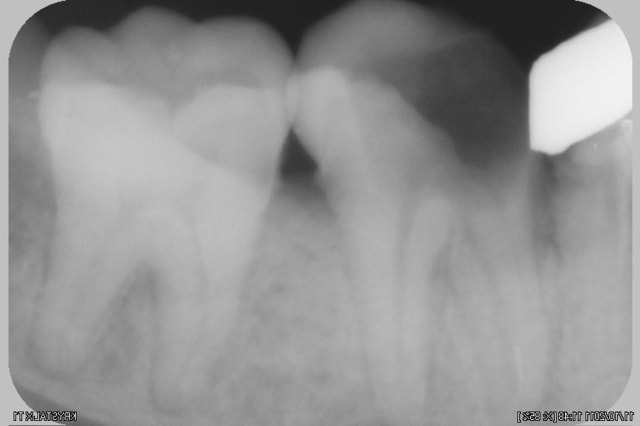

voila une lime cassée qui a engendré un probleme

est ce reparable?? si on va tenter du MTA, comment localiser spatialement la lesion????

Je ne comprends pas pourquoi tu voudrais utiliser du MTA. Sur la première radio on dirait que la limes est en dehors de la racine, le pronostic de la dent ne me parait pas très bon...

evidement MTA pour la reparation de la perfo